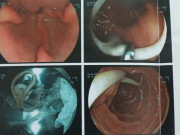

Không ngờ tình trạng thị lực mắt phải của Tiểu Hân ngày càng kém và tháng trước đột nhiên không nhìn thấy. Đến lúc này bố mẹ mới vội vàng đưa Tiểu Hân đến bệnh viện để kiểm tra. Sau khi kiểm tra bác sĩ phát hiện, mắt phải của cô bé chỉ nhìn thấy trong phạm vi 15cm. Qua siêu âm B phần mắt, bác sĩ thấy đáy mắt chảy máu nghiêm trọng, võng mạc cũng bị bong ra, cần phải phẫu thuật ngay lập tức. Tiểu Hân được chẩn đoán mắc bệnh giun đũa ở mắt.

Theo báo cáo, bệnh giun đũa ở mắt là do loại côn trùng có tên Toxocara ở chó, mèo gây ra. Đại đa số bệnh nhân tái phát ở mắt, triệu chứng chủ yếu là suy giảm thị lực. Sau phẫu thuật, bác sĩ hỏi các thành viên trong gia đình Tiểu Hân thì được biết, hóa ra trong nhà cô bé có nuôi một con chó, cô bé thường xuyên tiếp xúc và chơi với con chó.

Vài ngày trước, Tiểu Hân đến bệnh viện kiểm tra sau phẫu thuật, thị lực mắt bên phải của cô bé Tiểu Hân đã hồi phục thêm 0.05. Điều không may mắn là do đứa trẻ phát hiện bệnh tương đối muộn, ký sinh trùng đã phá hủy võng mạc, dẫn đến tổn thương không thể hồi phục lại bình thường.

Khi ấu trùng đến các mạch máu nhỏ hơn trong cơ thể của chúng ta, chúng có thể xuyên qua thành máu để vào cơ quan khác. Vì các mạch máu trong mắt nhỏ hơn cơ thể ấu trùng, ấu trùng có thể xâm nhập vào các mạch máu và xâm chiếm mắt. Theo thống kê, 80% bệnh nhân bị nhiễm giun đũa ở mắt là trẻ em dưới 16 tuổi. Giun đũa trắng sẽ trực tiếp phá hủy thủy tinh thể, võng mạc, màng đệm và các cấu trúc mắt khác, gây viêm, dẫn đến nhược thị, mù lòa nghiêm trọng và thậm chí gây teo nhãn cầu…